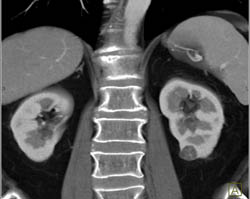

1 Cm Renal Cell Carcinoma